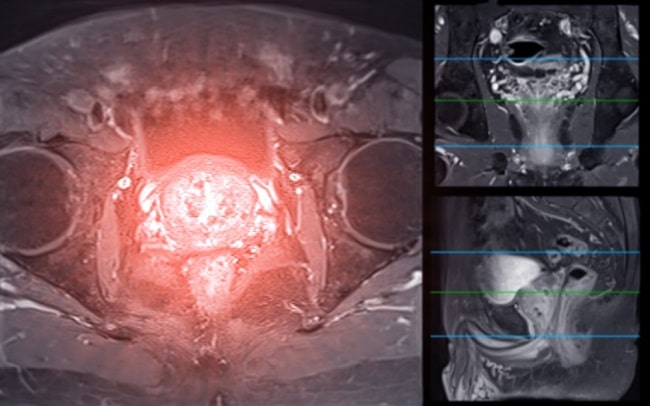

Metode: Dalam sebuah studi berbasis populasi yang dimulai sejak tahun 2015, peneliti mengikutkan pasien laki-laki berusia antara 50-60 tahun untuk menjalani skrining prostate-specific antigen (PSA). Pasien laki-laki dengan kadar PSA 3 ng/ml atau lebih akan menjalani pemeriksaan MRI.

Tahap pertama dari studi ini adalah pemeriksaan PSA. Hasil PSA yang yang kurang dari 3 ng/ml akan diarahkan untuk skrining PSA ulang setelah 2, 4, atau 8 tahun bergantung pada kisaran hasil PSA pasien. Apabila pada skrining ulang didapatkan kadar PSA lebih dari 3 ng/ml, maka akan dilakukan MRI sesuai dengan algoritma. Untuk pasien yang didapatkan kadar PSA lebih dari 3 ng/ml, baik pada kelompok biopsi berbasis MRI maupun kelompok biopsi sistematik, akan dilakukan MRI prostat terlebih dahulu.

Pada kelompok biopsi sistematik, pasien dengan hasil apapun dari MRI akan dilanjutkan dengan biopsi. Sementara itu, pada kelompok biopsi berbasis MRI, pasien hanya akan dibiopsi apabila ditemukan lesi mencurigakan dari pemeriksaan MRI atau bila kadar PSA lebih dari 10 ng/ml. Hasil pencitraan MRI akan diinterpretasikan oleh 2-4 dokter ahli radiologi yang berpengalaman lebih dari 5 tahun dalam hal MRI prostat.